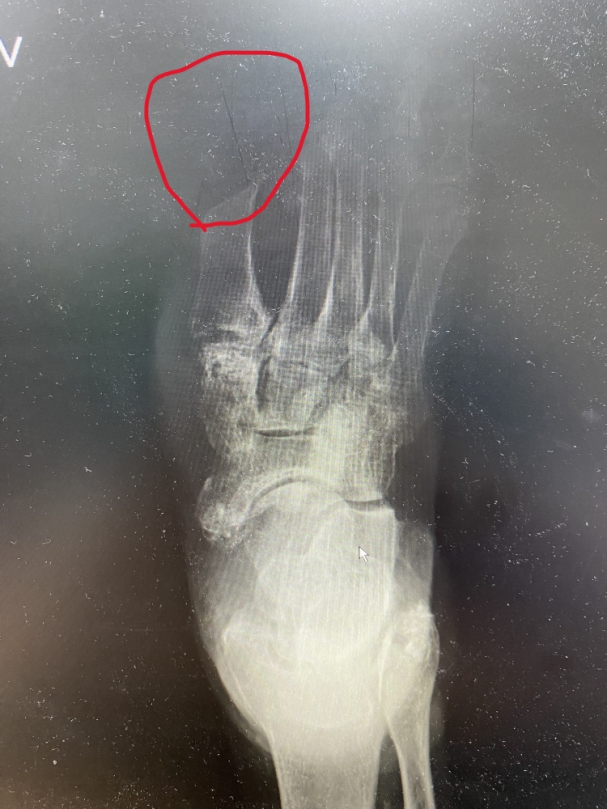

石姓男子糖尿病有十餘年病史,腳部神經病變沒痛感,2年多,腳底傷口不但有1元硬幣的大小,且易造成細菌感染,沿韌帶和筋膜往上穿透腳背,腳背出現10元硬幣大小的潰爛傷口,右腳踵得像「麵龜」,還發出惡臭,石姓男子痛得無法走路,今年二月中旬才到員榮就醫。

鄭文昌主任說,石姓男子除穿透腳背外,細菌沿著脛前的韌帶感染到右小腿,合併骨髓炎及壞死性肌膜炎,醫護人員先將感染部位切開,將壞死的組織、韌帶、骨骼和腳底病毒性疣清除外,並以手術清創,切開足底傷口,發現有兩個「竇道」,其中一個直通腳背,另一個從腳底往右小腿沿伸,經剪開後發現,右小腿脛骨韌帶被膿瘍包覆,長約30公分,韌帶也因壞死而切除。